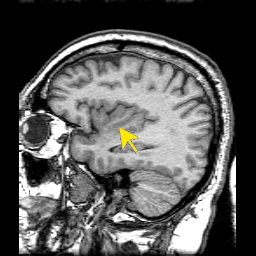

측두두정엽과 중간전두이랑. 출처는The Whole Brain Atlas

| 2주전 네이처에는 발표된 홍콩대 리하이 교수 팀의 연구 결과(관련기사)에 따르면 독서장애를 일으키는 뇌 부위가 문화에 따라 다르다. 알파벳 같은 소리글자를 못읽는 건 글자를 소리로 바꿔주는 좌뇌 측두두정엽에 문제가 있기 때문이고, 한자처럼 뜻글자를 못읽는 건 모양과 뜻을 연결시켜주는 좌뇌 중간전두이랑에 문제가 있기 때문이다. 그래서 어느 나라 말은 읽고 다른 나라 말은 못 읽는 경우가 생긴다고. |